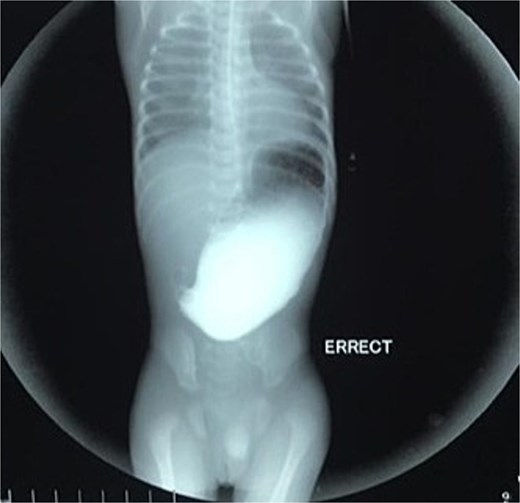

Initial management included nil per oral, fluid resuscitation, and nasogastric tube insertion. Laboratory investigations were unremarkable. Plain abdominal radiography revealed a single gastric air bubble with no distal gas, consistent with gastric outlet obstruction (Fig. 1). An upper gastrointestinal contrast study confirmed pyloric obstruction, with no contrast passing into the duodenum (Fig. 2).

The diagnosis of PA is typically confirmed postnatally based on clinical presentation, radiographic findings, and intraoperative exploration. Non-bilious vomiting, abdominal distension, and failure to pass stool are common clinical features, as seen in our patient [8]. Plain abdominal radiography often reveals a single gastric air bubble with no distal gas, while contrast studies demonstrate failure of contrast to pass beyond the pylorus, as observed in our case [9]. These findings are consistent with gastric outlet obstruction, which is pathognomonic for PA.